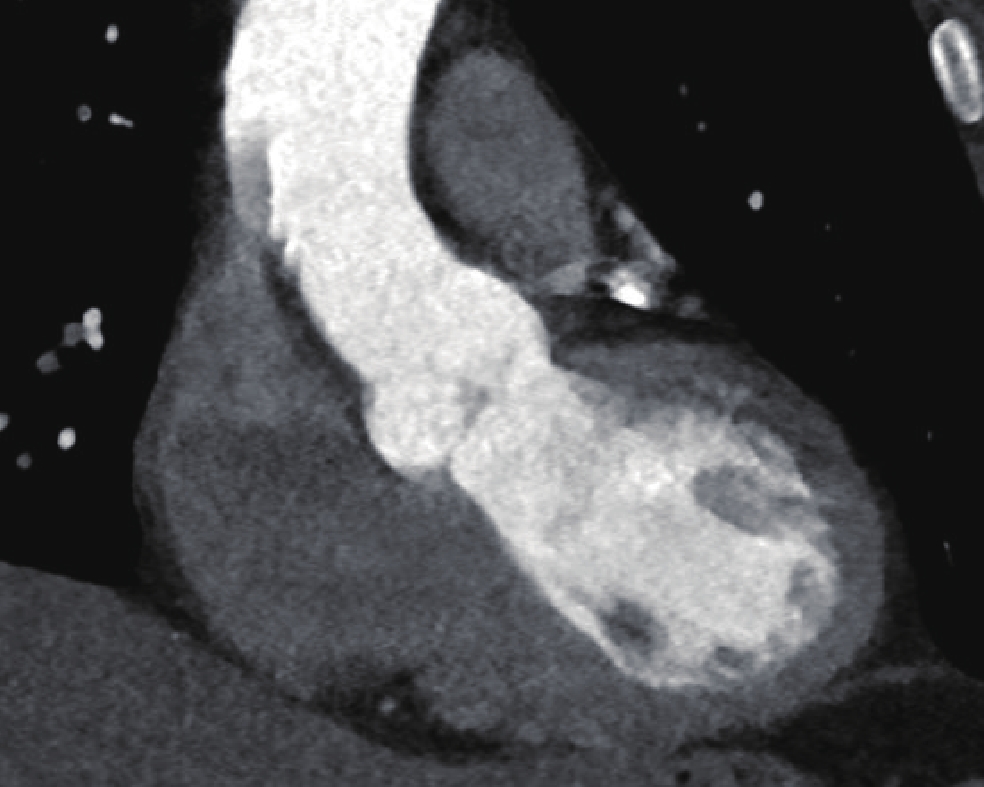

• 摘要: 目的:探讨不同扫描模式对胸主动脉CTA图像质量和辐射剂量的影响。方法:回顾性分析未应用心电门控技术的30例胸主动脉CTA(组1,对照组),使用回顾性心电门控的30例冠脉CTA重建舒张期(组2)和收缩期(组3)时相,30例应用宽曝光脉冲前瞻性心电门控技术(组4)共4组图像的质量和辐射剂量。分别记录、计算4组的图像质量客观指标CT值、噪声、CNR和辐射剂量指标CTDIvol。对图像质量进行四分法主观评价。对主客观指标分别统计分析。结果:客观指标CNR组1与组2、3、4均有差异,组2、3、4间均无差异;主观评分两两比较组2~4显著高于组1,组2~4间无差异。非门控组(组1)、回顾门控组(组2和组3)和前瞻门控组(组4)的CTDIvol分别为13.70(11.87,16.58)、12.62(10.03,15.01)、11.54(8.92,15.56),差异无统计学意义。结论:在胸主动脉CTA中推荐使用窄曝光脉冲的前瞻性心电门控收缩期或舒张期扫描,可显著提高胸主动脉心脏段图像质量并降低辐射剂量。

Abstract: Objective: This study aimed to compare the effects of different scanning modes on image quality and radiation dose in thoracic aortic computed tomography angiography (CTA). Methods: The image quality and radiation dose of 30 cases of thoracic aortic CTA (Group 1, control group), 30 cases of retrospective CTA diastolic phase (Group 2) and systolic phase (Group 3), and 30 cases of wide-exposure pulse prospective electrocardiogram (ECG) (Group 4) were retrospectively analyzed. The CT value, noise, contrast-to-noise ratio (CNR), signal-to-noise ratio (SNR), and radiation dose (volume CT dose index CTDIvol) were recorded and measured. The image quality was evaluated subjectively using the four points method. The subjective and objective indicators were analyzed statistically. Results: No differences were observed in the objective indexes of noise, CNR and SNR among the groups. The subjective score of pairwise comparison of Groups 2~4 was significantly higher than that of Group 1, and no difference was observed among Groups 2~4. The CTDIvol values of the non-gated group (Group 1), retrospective gated groups (Groups 2 and 3), and prospective gated group (Group 4) were 13.70 (11.87,16.58), 12.62 (10.03,15.01), and 11.54 (8.92,15.56), respectively, without a statistically significant difference.